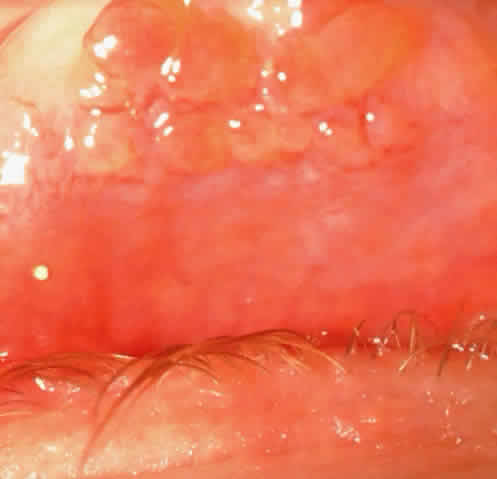

CONJUNCTIVA Patients with VKC may be divided into two groups based on clinical presentation: palpebral vernal and limbal vernal. Palpebral vernal involves the upper tarsal conjunctiva and is characterized by cobblestone papillae (i.e., papillae that have enlarged, often having flattened tops (Fig. 1). Papillae can be distinguished from follicles by their red centers; these centers consist of the dilated blood vessel at the core of the papilla surrounded by inflammatory cells. A sequela that may occur in VKC is conjunctival scarring that has a lacy appearance at the base of the old papillae. Although rare, there may be lacy scarring that extends superiorly into the fornix (Fig. 2). On rare occasions there may be conjunctival cysts (Fig. 3) and enough scarring to cause symblepharon formation. Fibrin that is enhanced by heat may accumulate on the giant papillae and is known as the Maxwell-Lyons sign.4